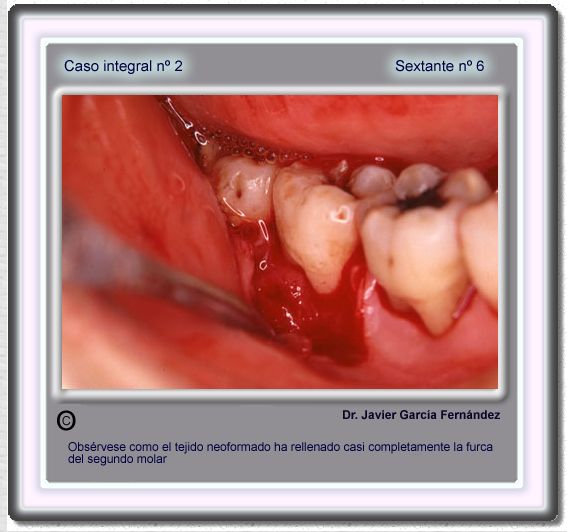

image 83